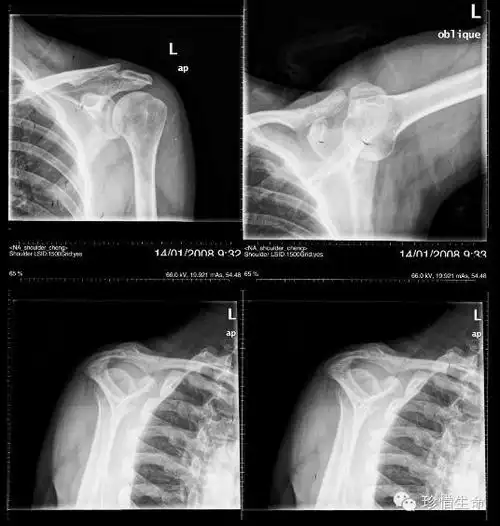

肩关节疼痛肩关节正侧位平片未见明显异常

术后左肩x线侧位片

不同肩关节x线投照位

肩关节x线检查体位大全